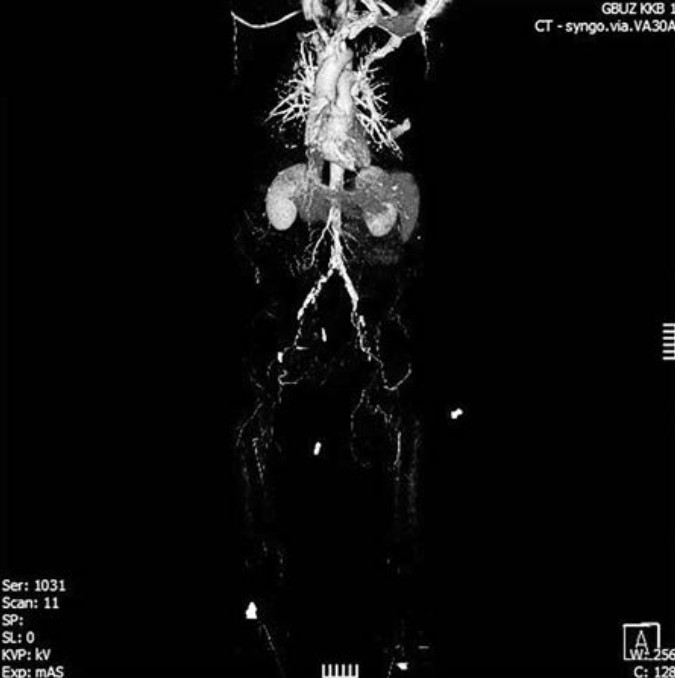

По ангиографии артерий нижних конечностей подтверждается уровень окклюзии. Бедренные, подколенные и берцовые артерии проходимы (рис. 2).

Рис. 2. Ангиография артерий нижних конечностей.